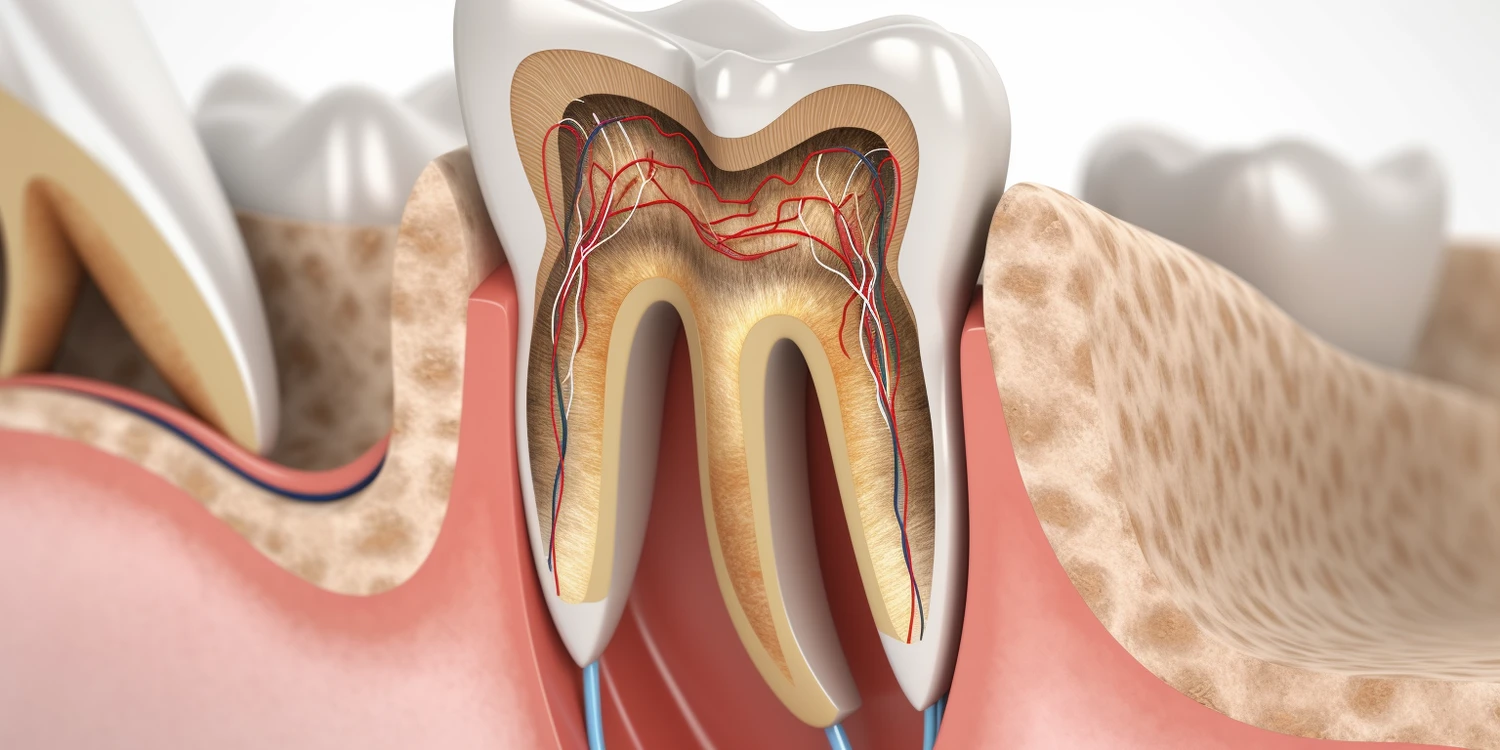

Dentysta nie zajmuje się wyłącznie zębami; jego zakres pracy obejmuje również inne aspekty zdrowia jamy ustnej oraz tkanek otaczających zęby. Stomatologia to dziedzina medycyny skupiająca się na diagnostyce i leczeniu schorzeń związanych zarówno ze zębami, jak i dziąsłami czy błoną śluzową jamy ustnej. Dentyści przeprowadzają zabiegi związane z leczeniem chorób dziąseł, takich jak zapalenie dziąseł czy paradontoza, które mogą prowadzić do utraty zębów jeśli nie zostaną odpowiednio leczone. Ponadto dentyści zajmują się także diagnostyką nowotworów jamy ustnej oraz innymi schorzeniami tkanek miękkich w obrębie jamy ustnej.